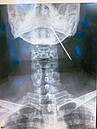

8公分長鋼釘體內迷航3年 男咳嗽就醫才發現 2020/03/12 10:35 一名男快遞員因咳嗽就醫,經X光檢查發現他左頸靠近下巴的軟組織插了一根八公分長的鋼釘,這名快遞員回想十五年前右肩鎖骨曾骨折打過鋼釘,主治醫師調閱快遞員病歷,懷疑鋼釘鬆脫... X光 新奇 鋼釘 骨折 咳嗽 快遞員 人氣: 1551